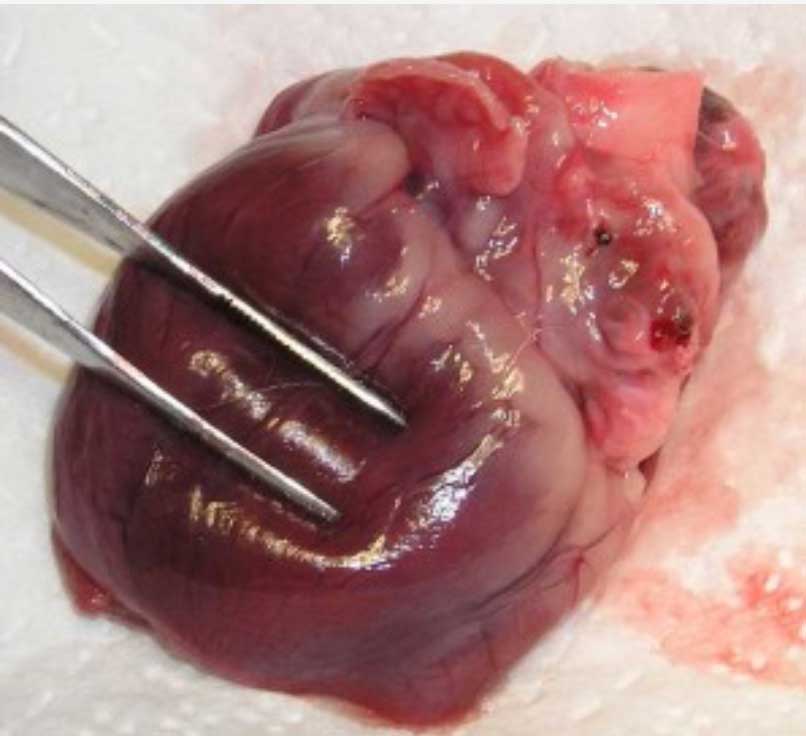

Heart Disease

Heart disease is an important problem, especially dilated cardiomyopathy. This is a serious disease and you need to be aware of it by following the cardiomyopathy link.

This heart has dilated cardiomyopathy as evidenced by the flabby ventricle under the forceps

Other heart problems include atrial septal defect.

Most heart problems are diagnosed in younger dogs with signs of exercise intolerance and coughing, though heart disease is certainly not the only cause of those signs.

Heart diseases are sometimes detected on physical exam using a stethoscope. If your Boxer does not seem to be an energetic as you would expect, tires easily, or seems excessively tired after mild exercise, this needs to be addressed with a cardiac workup.